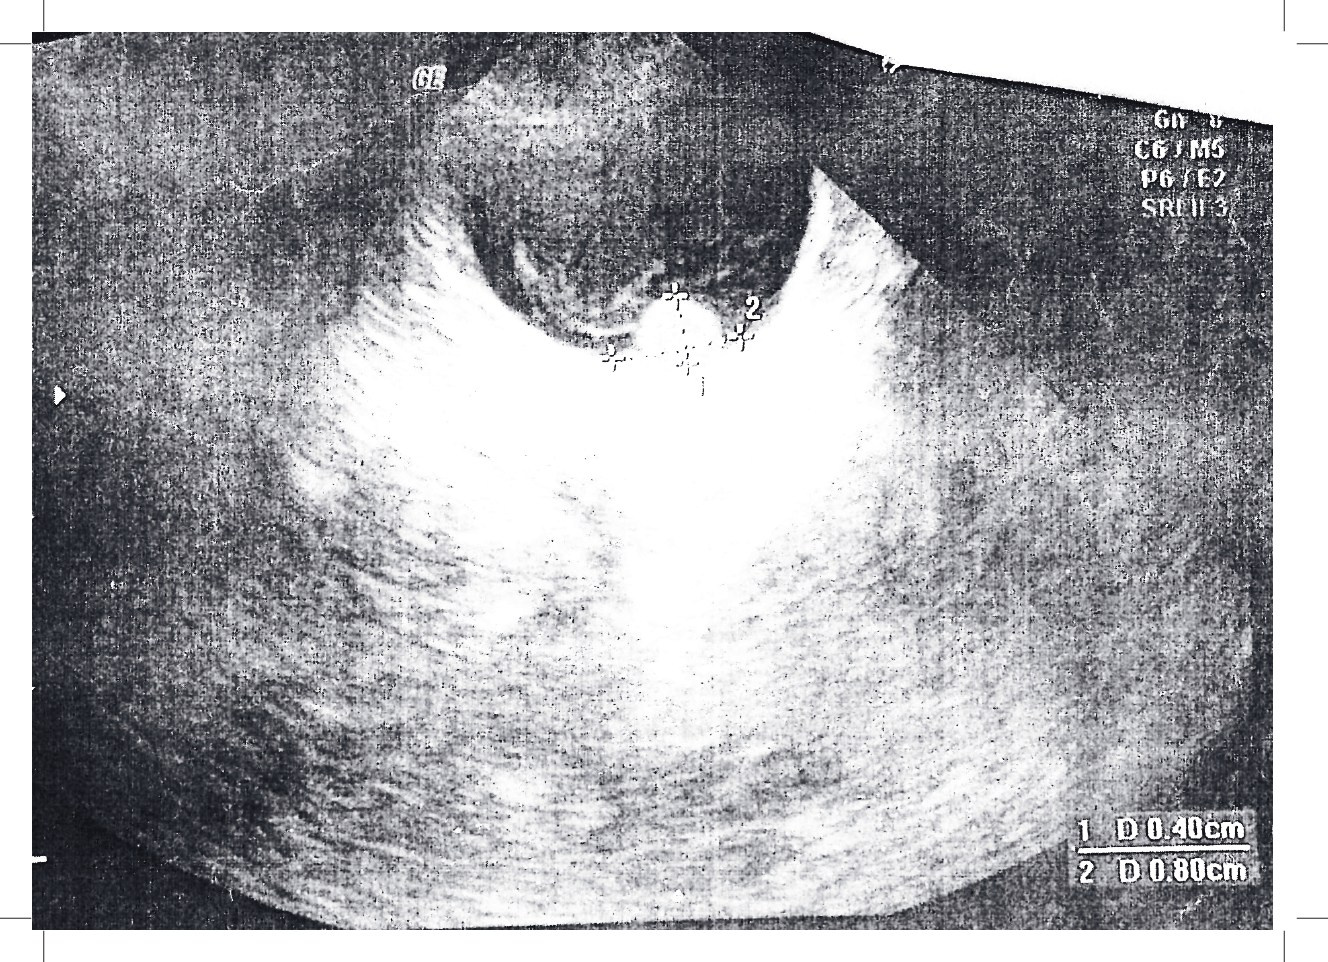

Валерия исследует физическую и эмоциональную трансформацию через призму личного опыта борьбы с заболеванием. Процесс исцеления и восстановления зрения становится метафорой внутреннего возрождения и смещения восприятия. Этот проект идеально дополнит тему выставки, так как он показывает, как болезнь меняет человека, но также и как он находит внутреннюю опору в новой реальности. Лера отражает путь от разрушения к восстановлению, создавая визуальный дневник своих переживаний.